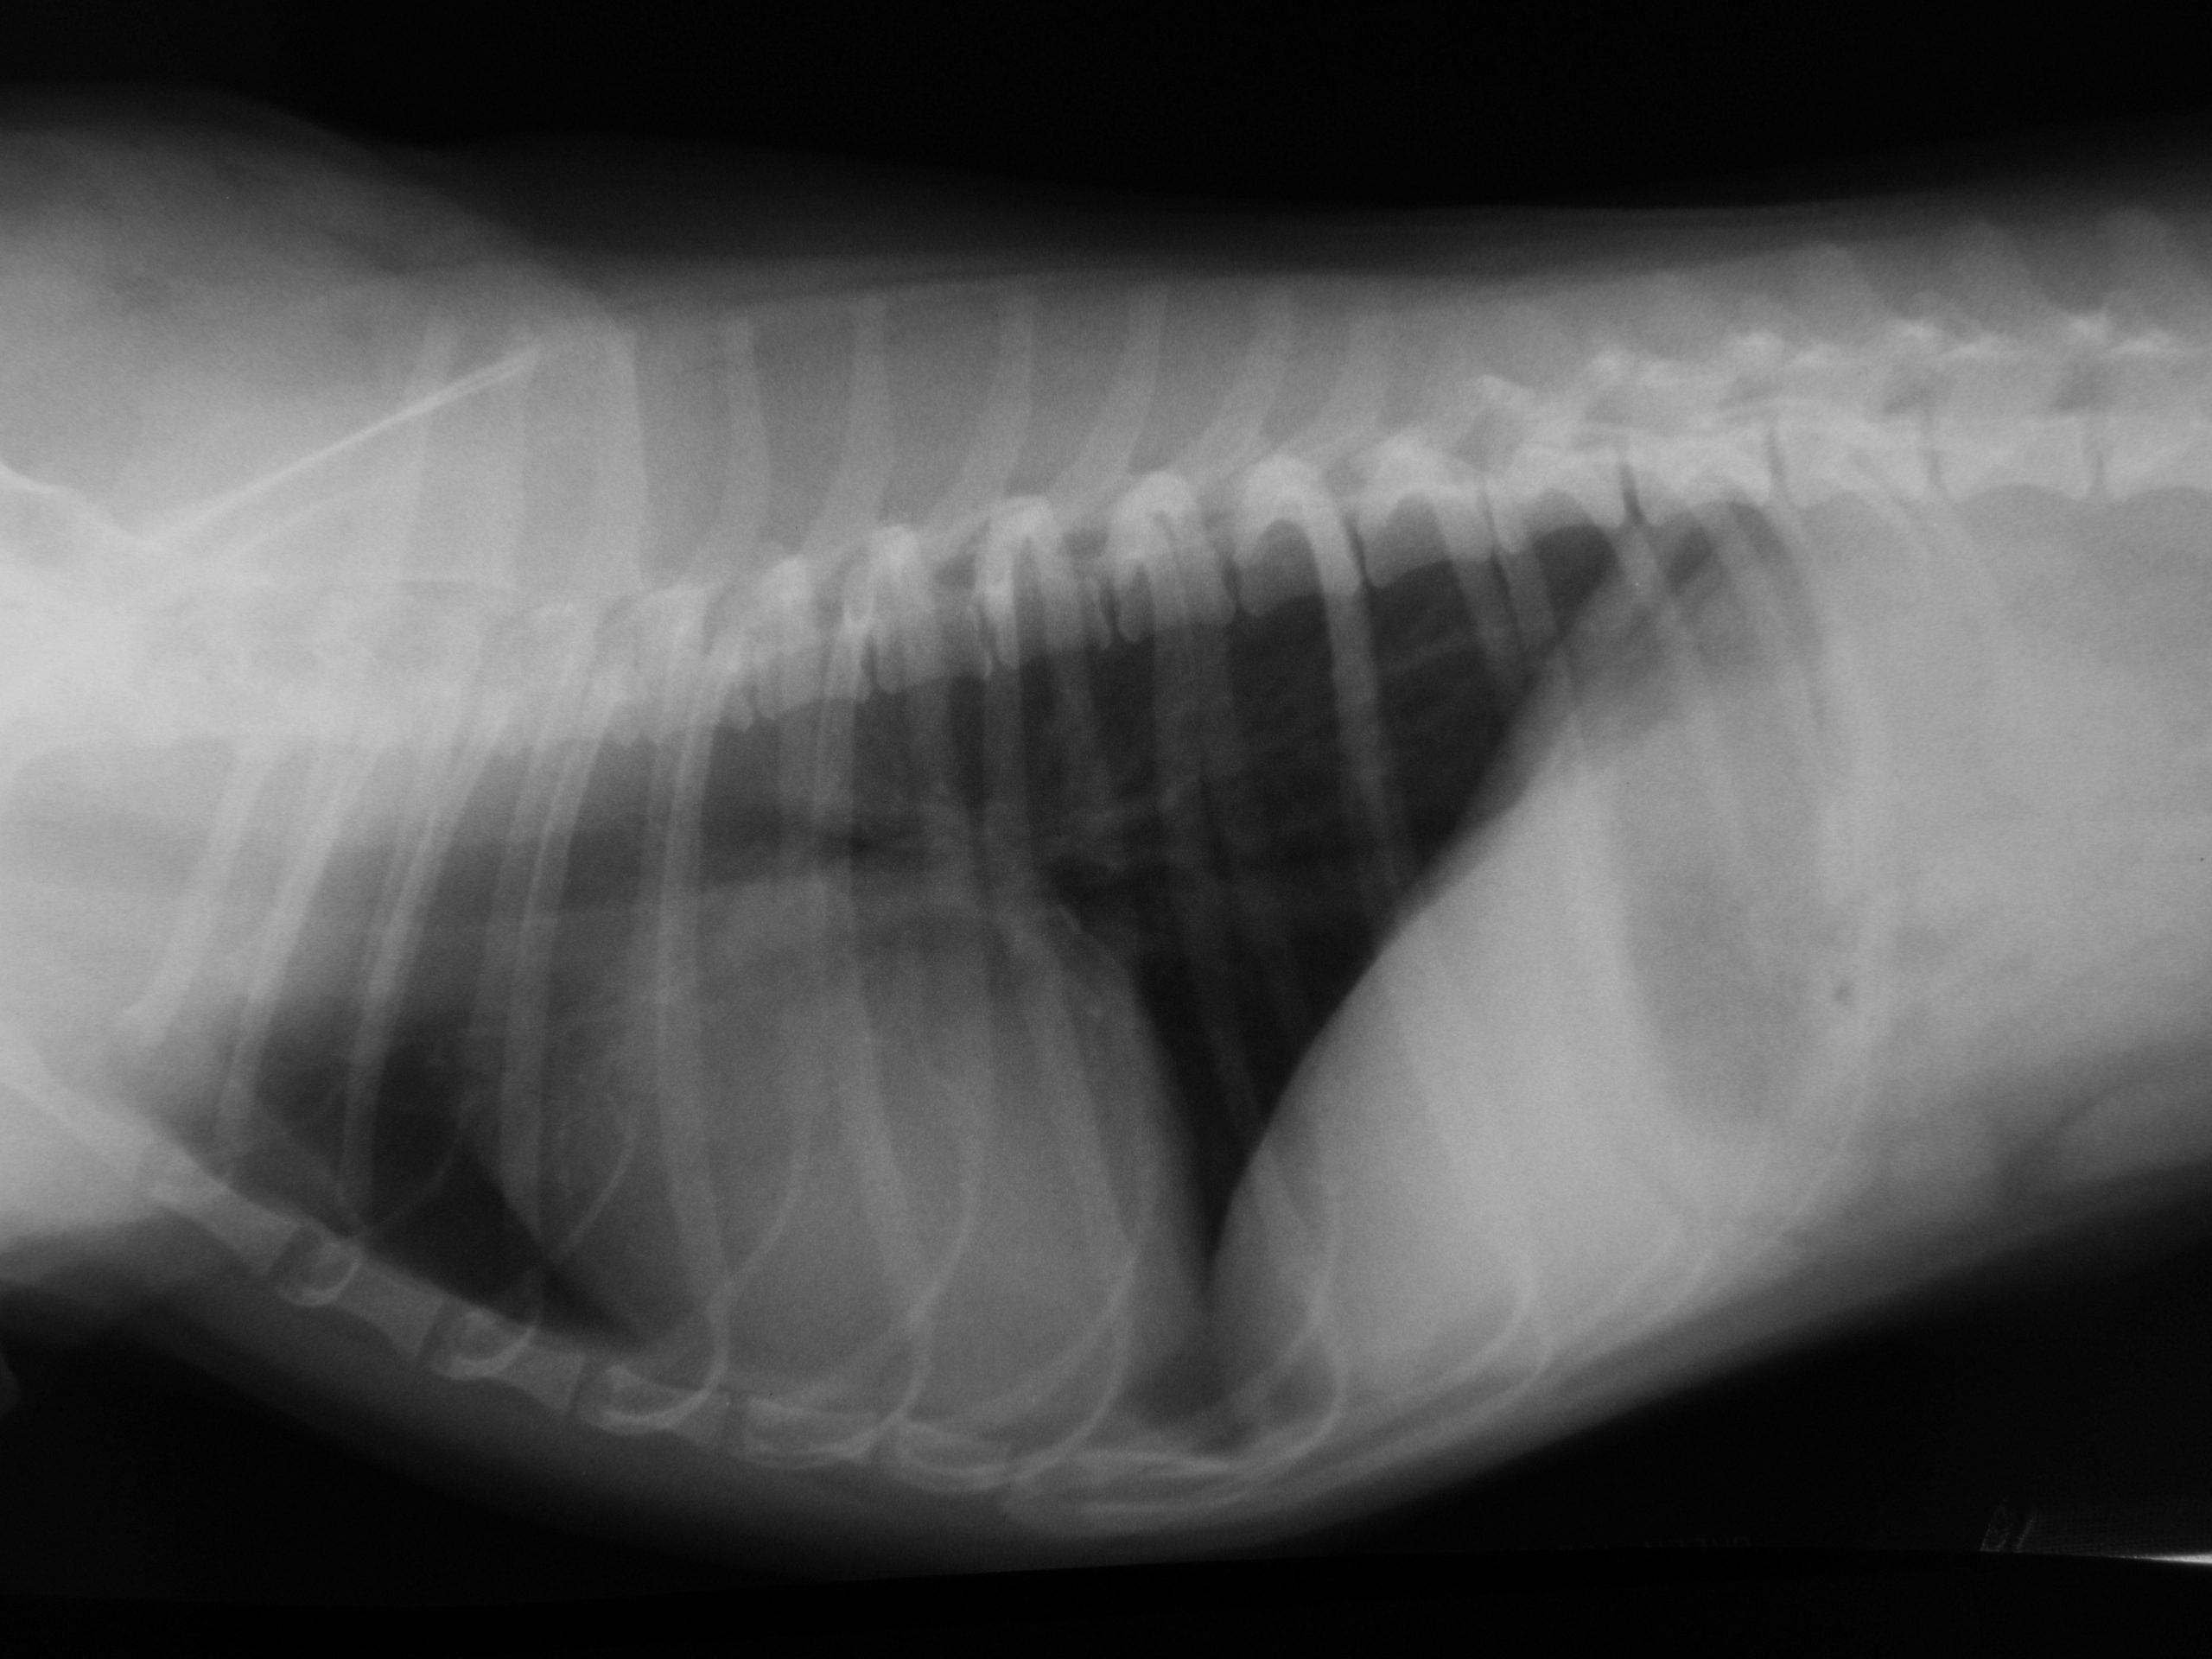

A 6-year-old FS Shih Tzu presented for exercise intolerance and cyanosis under stress. The clinical exam was otherwise unremarkable. A slight right and left sided murmur was auscultated. Right sided cardiomegaly was noted on radiographs. Radiographs (Image 1): generalized right sided cardiomegaly is noted. There is no evidence of pulmonary congestion. The lung pattern is unremarkable.